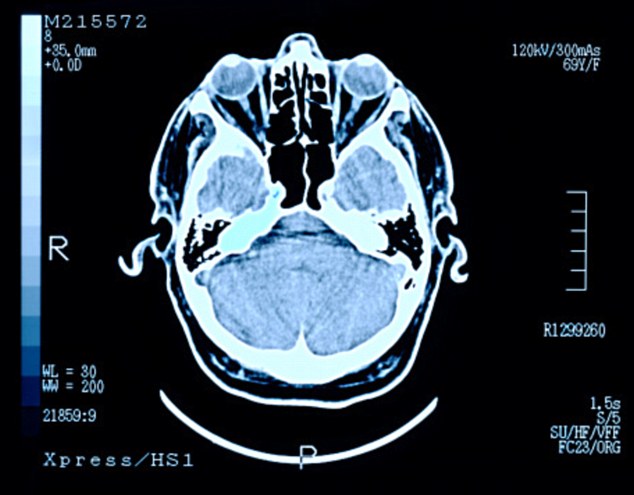

Physicians should not immediately order routine scans for low-back pain unless they observe features of a serious underlying condition, researchers in the Oregon Evidence-Based Practice Center at Oregon Health & Science University report. Their findings are published in this week's edition of the The Lancet.